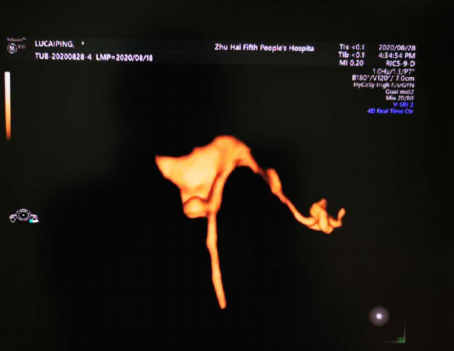

超声造影显示:双侧输卵管通畅

四维子宫输卵管超声造影是一种最新的超声成像技术,采用新型声学造影剂注入宫腔,在三维/四维超声监测下能清晰直观地显示宮腔及输卵管的走行、通畅程度,是评价子宫畸形及输卵管形态学及通畅性最重要的检查方法。另外,经过造影可疏通宫腔內及输卵管内小的粘连带,故同时具有治疗作用。由此可见,该技术具有其它检查方法无法比拟和替代的强大优势,为不孕症患者带来了福音。

该技术具有实时、安全、无辐射、重复性好、可同时疏通治疗、患者检查次月即可受孕等优势,除评估输卵管通畅性,还可有机整合二维超声、三维超声及宫腔水造影等技术,系统评估子宫病变、输卵管病变和卵巢病变。